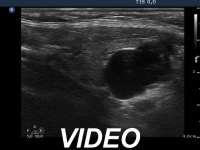

Ultrasonography: The thyroid was minimally-moderately hypoechogenic and presented fibrosis. There was a cystic lesion in the lower dorsal part of the right thyroid bed.

Twelve mL cystic fluid was aspirated. There were no cells on the smear.